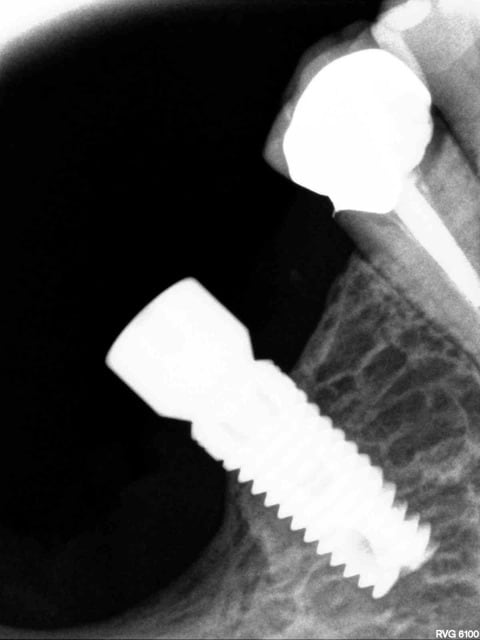

La semaine dernière j'ai posé un implant sur un os extrêmement dur et il m'a été impossible de le visser entièrement malgré le protocole os dur avec forêt d'evasement etc.

S'agissant d'un implant juxtaosseux ,les micros pires sont hors de l'os .

J'ai quand même refermé mais je le regrette .

Lors de la dépose d'anciens implants j'avais te tendance à faire confiance au phénomène osteoclasique après utilisation de tourne à l'envers mais j'ai eu pas mal de déboires. C'est la première fois que je dois déposer un implant fraîchement posé. S'agit il du même phénomène lié au forage qui crée une première résorption autour de l'implant avant remodelage et osteointegration? Je le suppose mais je voudrais savoir combien de temps dure cette phase. C'est la première fois que je suis confronté à un os si dur. 36 extraite depuis plus de 20 ans.

Pour moi dans ce cas, l'os crestal a ete traumatise lors du vissage, et meme si tu forces pour le rentrer a fond plus tard, tu verras 1 an apres que l'os sera redescendu sous les microspires.

Alors autant ne rien toucher pour moi.

Concernant la force pour ressortir un implant osteointégré, meme ne tenant que sur 4 mm, elle est INCROYABLEMENT FORTE.

J'ai eu le cas sur une patiente avec implants sans probleme depuis 2006, debut de craterisation en 2014.

J'ai utilise le tourne a gauche d'anthogyr, et malgre le detourage a la fraise sur la profondeur la plus grande possible, j'ai bien cru que soit l'instrument soit la mandibule allaient rompre.

En fait ca ressort quand l'os autour de l'implant se rompt dans son epaisseur. L'os est reste collé sur l'implant retire.